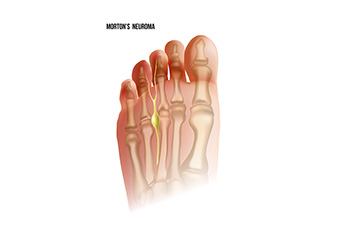

What is Morton's Neuroma?

Morton’s neuroma, (also referred to as Morton’s metatarsalgia, Morton’s neuralgia, plantar neuroma or intermetatarsal neuroma) is a condition that is caused when the tissue around one of the nerves between your toes begins to thicken. This thickening can result in pain in the ball of the foot. Fortunately, the condition itself is not cancerous.

Morton’s neuroma affects women more often than men with a ratio of 4:1. It tends to target women between the age of 50 and 60, but it can occur in people of all ages. There are some risk factors that may put you at a slightly higher risk of developing the condition. People who often wear narrow or high-heeled shoes are often found to be linked to Morton’s neuroma. Additionally, activities such as running or jogging can put an enormous amount of pressure on the ligament and cause the nerve to thicken.

There usually aren’t any outward symptoms of this condition. A person who has Morton’s neuroma may feel as if they are standing on a pebble in their shoe. They may also feel a tingling or numbness in the toes as well as a burning pain in the ball of their foot that may radiate to their toes.

In order to properly diagnose you, the doctor will press on your foot to feel for a mass or tender spot. He may also do a series of tests such as x-rays, an ultrasound, or an MRI. X-rays are usually done to rule out any other causes for your foot pain such as a stress fracture. Ultrasounds are used to reveal soft tissue abnormalities that may exist, such as neuromas. Your podiatrist may want to use an MRI in order to visualize your soft tissues.

There are three main options for treatment of Morton’s neuroma: Injections, decompression surgery, and removal of the nerve. Injections of steroids into the painful area have been proven to help those with Morton’s neuroma. Decompression surgery has been shown to relieve pressure on the affected nerve by cutting nearby structures such as the ligaments in the foot. Another treatment option would be to surgically remove the growth to provide pain relief.

If you suspect that you have Morton’s neuroma you should make an appointment with your podiatrist right away. You shouldn’t ignore any foot pain that lasts longer than a few days, especially if the pain does not improve.

Common Symptoms of Morton’s Neuroma

Morton's neuroma is a painful condition that affects the ball of the foot, specifically the area between the third and fourth toes. This condition involves the thickening of the tissue surrounding a nerve leading to the toes, usually caused by irritation or compression. The hallmark symptom of Morton's neuroma is a sharp, burning pain or the sensation of a small, pebble-like object under the ball of the foot. As the condition progresses, individuals may experience numbness, tingling, or a feeling of swelling in the toes. The pain tends to worsen with activities like walking or wearing tight shoes, as these activities compress the affected nerve. Morton's neuroma is often more prevalent in women and individuals who frequently wear high heels or engage in activities that put repetitive pressure on the forefoot. Morton’s neuroma is treated by a podiatrist. If you are experiencing symptoms of this condition, it is suggested that you schedule an appointment with this type of doctor who can accurately diagnose and treat Morton’s neuroma.

Morton’s neuroma is a very uncomfortable condition to live with. If you think you have Morton’s neuroma, contact Kellvan Cheng, DPM of Elite Foot & Ankle. Our doctor will attend to all of your foot care needs and answer any of your related questions.

Morton’s Neuroma

Morton's neuroma is a painful foot condition that commonly affects the areas between the second and third or third and fourth toe, although other areas of the foot are also susceptible. Morton’s neuroma is caused by an inflamed nerve in the foot that is being squeezed and aggravated by surrounding bones.

What Increases the Chances of Having Morton’s Neuroma?

- Ill-fitting high heels or shoes that add pressure to the toe or foot

- Jogging, running or any sport that involves constant impact to the foot

- Flat feet, bunions, and any other foot deformities

Morton’s neuroma is a very treatable condition. Orthotics and shoe inserts can often be used to alleviate the pain on the forefront of the feet. In more severe cases, corticosteroids can also be prescribed. In order to figure out the best treatment for your neuroma, it’s recommended to seek the care of a podiatrist who can diagnose your condition and provide different treatment options.